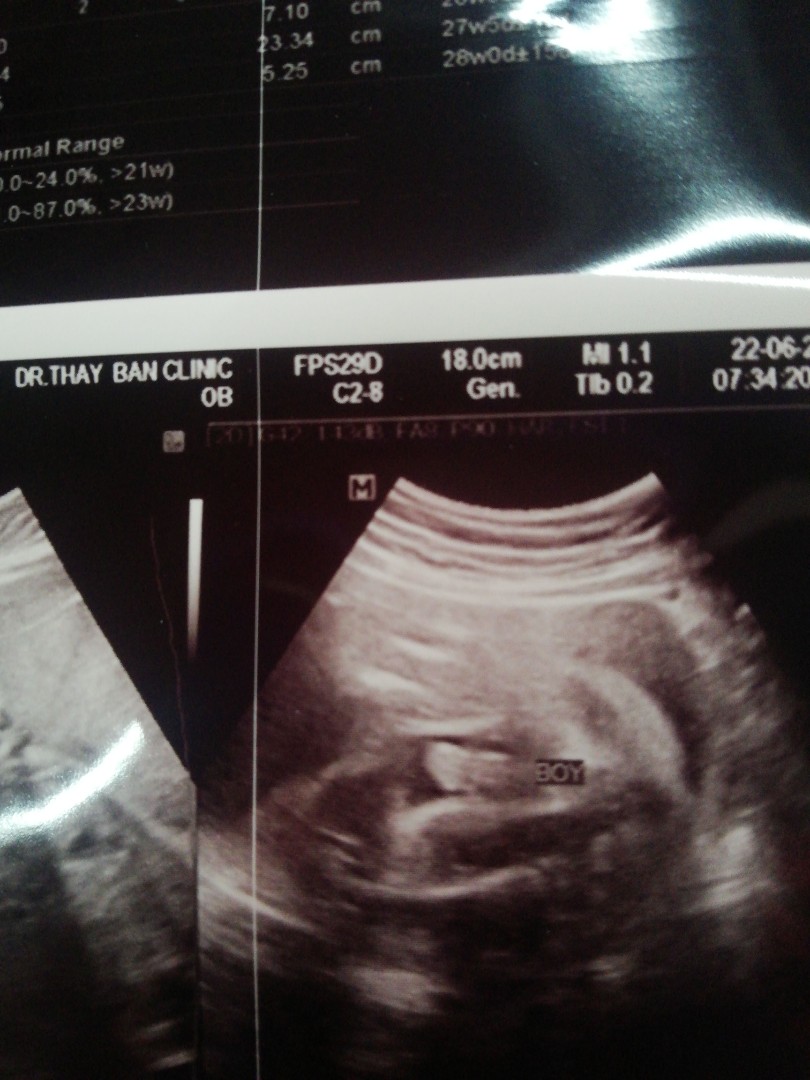

ใบอัลตร้าซาวด์

แม่ๆช่วยดูหน่อยคะ ผช.ใช่ไหมคะ หมอบอก ผช. บ้านไหนได้ ผช. ลงรูปใบซาวด์ให้ดูหน่อยคะ

ชายค่ะ

ผช. ค่ะ

ผ.ช ค่ะ

ผช. จ้า

ผช ค่ะ

ผช.จ้า

ผช.ค่ะ

ผชจ้า

ผช.คะ